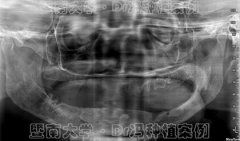

攻克种牙界“珠穆朗玛峰” 穗华口腔医

种植牙是目前很受欢迎的缺牙修复方式,不少缺牙者牙槽骨严重萎缩、骨量极少...【详细】

“穿颧种植”助六旬缺牙阿姨终结20多年假牙生活

种植牙是最佳的缺牙修复方式已经是不争的事实!但对骨质疏松、牙槽骨薄如指...【详细】

无牙颌也能种牙?穗华口腔医院穿颧种

穿颧种植技术一直被誉为是种植牙界珠穆朗玛峰式的顶级技术,也是很好的疑难...【详细】